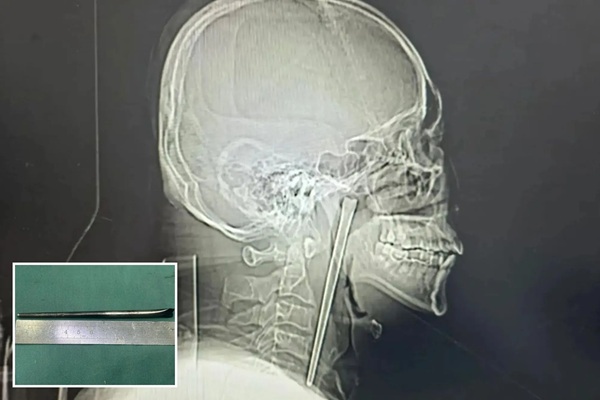

கடந்த 8 ஆண்டுகளாகத் தனது தொண்டையில் அந்த உலோகக் கம்பி இருப்பதை உணர்ந்த போதிலும், அவர் அதனைப் பெரிதாகக் கண்டுகொள்ளவில்லை. மது அருந்துவதால் ஏற்படும் சாதாரண அசௌகரியம் என்றே அவர் தன்னைத்தானே சமாதானப்படுத்திக் கொண்டுள்ளார். ஆனால், சமீப காலமாகக் காலையில் எழுந்திருக்கும் போதும், உணவை விழுங்கும் போதும் தாங்க முடியாத வலி ஏற்பட்டுள்ளது. வலி நிவாரணிகள் கொடுத்தும் பலன் அளிக்காததால், கடந்த மார்ச் 2026-ல் அவர் மீண்டும் டாலியன் நகராட்சி மத்திய மருத்துவமனைக்குச் சிகிச்சைக்காகச் சென்றார். அங்கு அவரைப் பரிசோதித்த மருத்துவர்கள், தொண்டையின் உள்பகுதியில் (Soft Palate) அந்த உலோகக் கம்பி செங்குத்தாக நிற்பதைக் கண்டு அதிர்ச்சியடைந்தனர்.

அறுவை சிகிச்சைக்கு வாங் தொடர்ந்து தயக்கம் காட்டியதால், மருத்துவர்கள் இம்முறை புதிய முயற்சியை மேற்கொண்டனர். அவரது கழுத்துப் பகுதியை அறுக்காமல், வாய் வழியாகவே எண்டோஸ்கோபி முறையிலான ஒரு சிறிய ‘குறைந்தபட்ச ஊடுருவல்’ (Minimally Invasive) அறுவை சிகிச்சையை மேற்கொண்டனர். இந்தச் சிக்கலான சிகிச்சையின் மூலம், சுமார் 8 ஆண்டுகளாகத் தொண்டையில் புதைந்திருந்த 12 செ.மீ நீளமுள்ள துருப்பிடிக்காத எஃகு சாப்ஸ்டிக் வெற்றிகரமாக அகற்றப்பட்டது. இவ்வளவு காலமும் அந்த உலோகக் கம்பி அவரது குரல் நாண்கள் அல்லது உணவுக்குழாயில் பெரிய காயங்களையோ, தொற்றுநோயையோ ஏற்படுத்தாமல் இருந்தது ஒரு பெரிய அதிசயம் என்று மருத்துவர்கள் கூறுகின்றனர்.